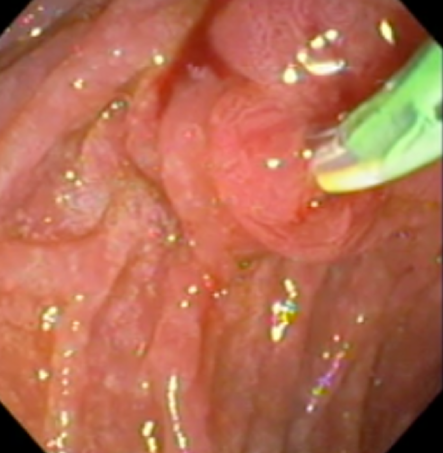

Estômago

O estômago é o local onde os alimentos são colocados para serem processados e liberados para o intestino delgado para serem absorvidos. Como é um órgão que produz ácido e pepsina outras substâncias importantes para manter a integridade e bom funcionamento do nosso organismo.

Ele pode sofrer processos inflamatórios superfícies , erosões e ulcerações e outras patologias benignas e malignas. É o local onde se aloja a bactéria Helicobacter pylori responsável por várias patologias que acometem o estômago